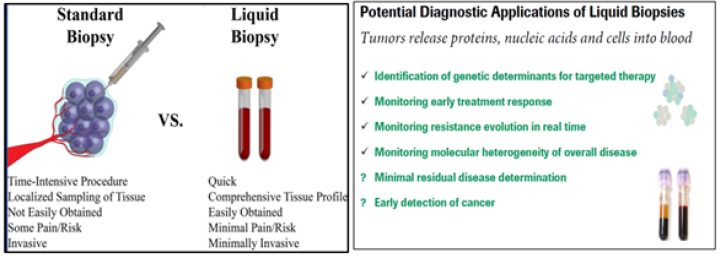

A unique example of the applications to unite the abovementioned technologies as applicable to PPO-related cancer monitoring and tumor progression is an approach named as Liquid Biopsy (Figure 7A, B).

Although tumor biopsies continue to be mandatory in cancer diagnosis and classification, several studies have demonstrated that liquid biopsies could be used as a potential tool for the detection of cancer-specific biomarkers. One of the main advantages is that circulating free DNA (cfDNA) provides information about intratumoral heterogeneity, reflecting dynamic changes in tumor burden. This minimally invasive tool has become an accurate and reliable instrument for monitoring cancer genetics as applicable to oncology practice.

Figure 7A&7B:Standard and liquid biopsies through the View of PPM/PPO. Liquid biopsies can be used to accurately screen for cancer in clinical practice. Traditional biopsies can be difficult to ob-tain but have been the predominant way to diagnose and understand cancer. Liquid biopsies are faster for doctors and easi-er for patients because they take blood samples rather than tissue samples. Liquid biopsy is a minimally invasive technology for detection of biomarkers. Circulating cancer cells or traces of the can-cer’s RNA or DNA in the blood can give clues about which treatments are most likely to work for that patient. Circulating nucleic acids are protected by extracellular micro-vesicles, mainly exosomes. New dedicated methods enable you to enrich and purify from this liquid biopsy: circulating free DNA (cfDNA), circulating small-RNA, circulating tumor cells (CTCs), extracellular mirco-vesicles (including exosomes) containing small-RNA, mRNA and DNA.